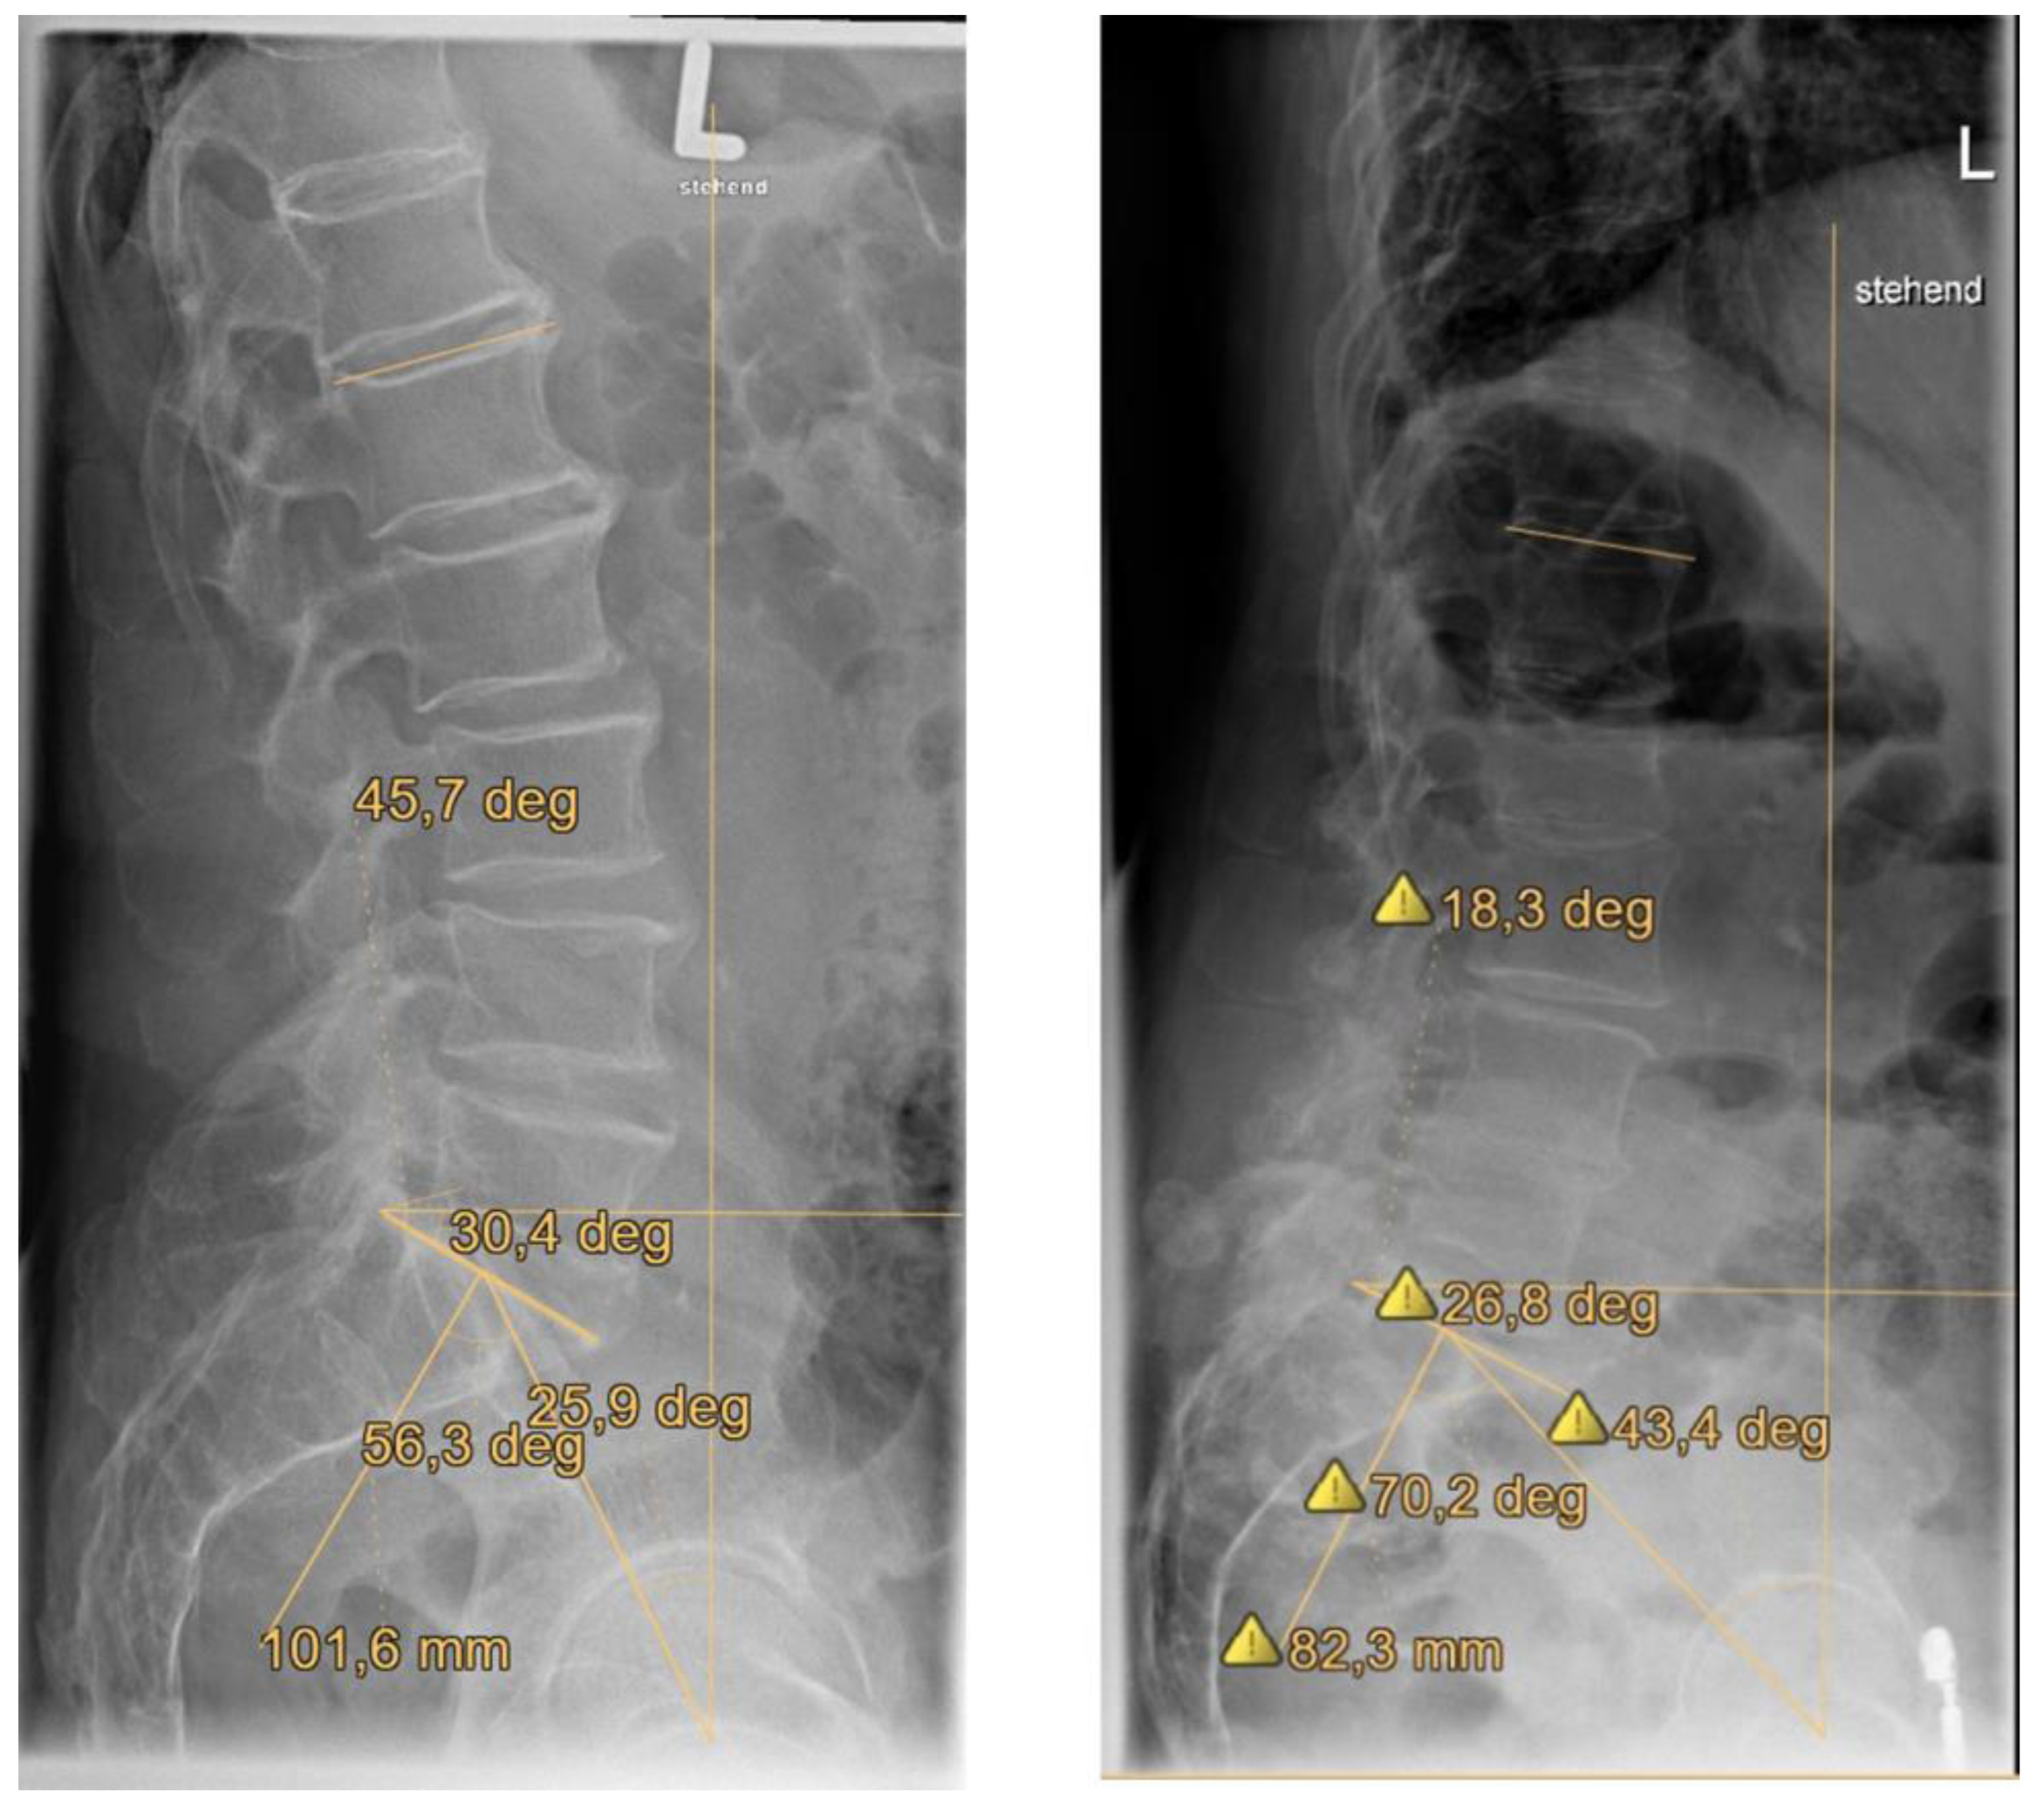

3.3. Spinopelvic Parameters

| Parameters | Degree | SD (Degree) |

|---|---|---|

| LL | 47.9 | ±14.4 |

| PT | 29.4 | ±8.8 |

| SS | 34.2 | ±10.4 |

| PI | 64.4 | ±12.9 |

| LLI | 0.7 | ±0.2 |